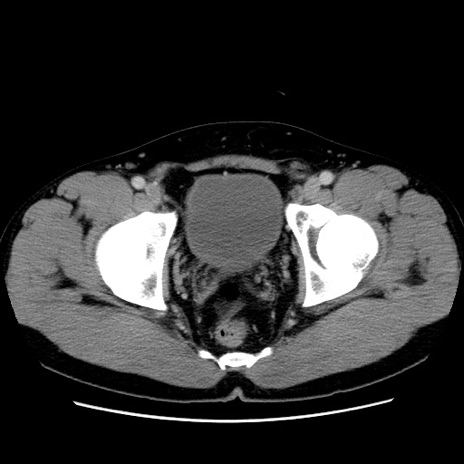

症例4(横断像)

【症例】30歳代男性

【主訴】腹痛、嘔吐

【現病歴】昨晩から突然の腹痛あり、その後嘔吐、軟便も出現。腹痛が改善しないため救急搬送となる。2日前にしめ鯖の食事歴あり。

【身体所見】意識清明、苦悶様、BP 135/90mmHg、BT 35.7℃、腹部:平坦、やや硬、心窩部〜臍部に自発痛、圧痛あり、筋性防御+、反跳痛-

【データ】WBC 8100、CRP 0.57